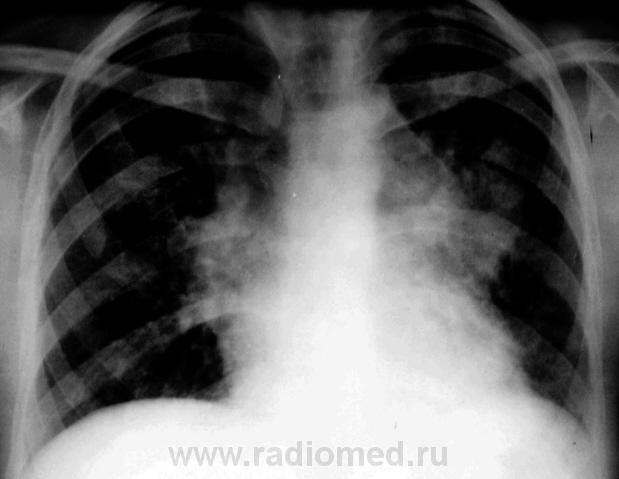

Пол пациента: Женский пол Тип патологии: Воспалительное заболевание неинфекционной природы Область исследования: Грудная клетка и верхние дыхательные пути Методы исследования: Rg Болеет около 3-х недель. Жалобы на одышку , сердцебиение. 10 дней принимала антибиотики. Возможно это сердечная патология? Бокового снимка нет. https://radiomed.ru/sites/default/files/styles/case_slider_image/public/user/12/1.Bod_..jpg?itok=E-KH1jBz https://radiomed.ru/sites/default/files/styles/case_slider_image/public/user/12/2.Bod_.jpg?itok=rzvtyFWz https://radiomed.ru/sites/default/files/styles/case_slider_image/public/user/12/3.Bod_..jpg?itok=2JC7feyE ID:1839 Втр, 16/03/2010 - 16:36 #1 tatyana Не на сайте Был на сайте: 4 года 1 месяц назад Зарегистрирован: 24.06.2009 - 08:33 Публикации: 2090 bogdan wrote: Возможно это сердечная патология? Вряд ли, скорее опухолевая "самоуверенность дилетантов - предмет зависти профессионалов" Втр, 16/03/2010 - 18:29 #2 ElenaG Не на сайте Был на сайте: 15 лет 7 месяцев назад Зарегистрирован: 23.02.2010 - 23:21 Публикации: 69 Хотелось бы узнать возраст пациентки.ятоже за онкологию,Хотя и правый корень кажется расширен.Не окажется ли это лимфоузлами? Втр, 16/03/2010 - 18:30 #3 Лукаш Не на сайте Был на сайте: 10 лет 3 месяцев назад Зарегистрирован: 05.03.2010 - 13:28 Публикации: 47 А может быть и саркоидоз или ЛГМ (возраст какой?). Есть признаки сдавления верхней полой вены? Ой, больной, что-то мне ваш снимок не нравится. Но ничего - щас мы в Фотошопе все подправим. Втр, 16/03/2010 - 20:19 #4 bogdan Не на сайте Был на сайте: 7 лет 1 месяц назад Зарегистрирован: 07.01.2010 - 16:14 Публикации: 45 Девушке 23 года Втр, 16/03/2010 - 21:04 #5 Петрович Не на сайте Был на сайте: 7 лет 2 месяцев назад Зарегистрирован: 22.03.2009 - 01:13 Публикации: 3908 А почему не сделана хотя бы левая боковая проекция? Болеет давно, клиника серьёзная. Пора уже и томограммы делать. Вон как средостение расширено. Неоднозначно всё Втр, 16/03/2010 - 23:53 #6 Лукаш Не на сайте Был на сайте: 10 лет 3 месяцев назад Зарегистрирован: 05.03.2010 - 13:28 Публикации: 47 Возраст молодой - надо исключать лимфогранулематоз: поискать периферические лимфоузлы, при нахождении - пропунктировать. Еще УЗИ ОБП - на предмет парааортальных л/у. Ой, больной, что-то мне ваш снимок не нравится. Но ничего - щас мы в Фотошопе все подправим.

А может быть и саркоидоз или ЛГМ (возраст какой?).

Есть признаки сдавления верхней полой вены?

Девушке 23 года

А почему не сделана хотя бы левая боковая проекция? Болеет давно, клиника серьёзная. Пора уже и томограммы делать. Вон как средостение расширено.

Возраст молодой - надо исключать лимфогранулематоз: поискать периферические лимфоузлы, при нахождении - пропунктировать.

Еще УЗИ ОБП - на предмет парааортальных л/у.